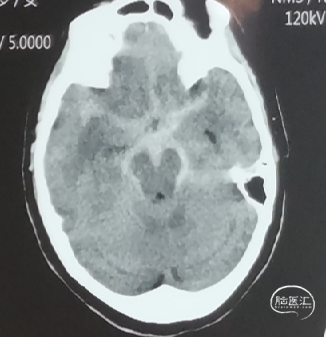

重度硬化患者不适合阻断

“二无”——术中无阻断。

• 动脉硬化重的患者阻断有脱斑块风险

• 阻断时间长的患者术后唤醒时间长、恢复慢

• 不破裂不阻断,无阻断不可强求